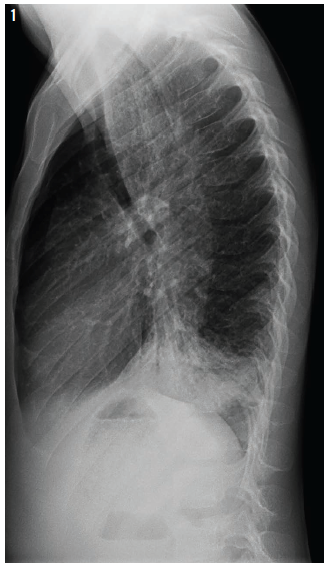

On further evaluation, further chest radiographs were ordered (Figure 1), along with computed tomography (CT) scan of the chest (Figure 2).

On further evaluation, the chest radiograph showed what appeared to be a dilated and fluid-filled structure in the boy’s mediastinum (Figure 1). The CT of the chest showed bilateral lower-lobe infiltrates, along with the unexpected finding of a severely dilated, fluid-filled esophagus (Figure 2), which correlated with chest radiography findings. This raised suspicion for achalasia.